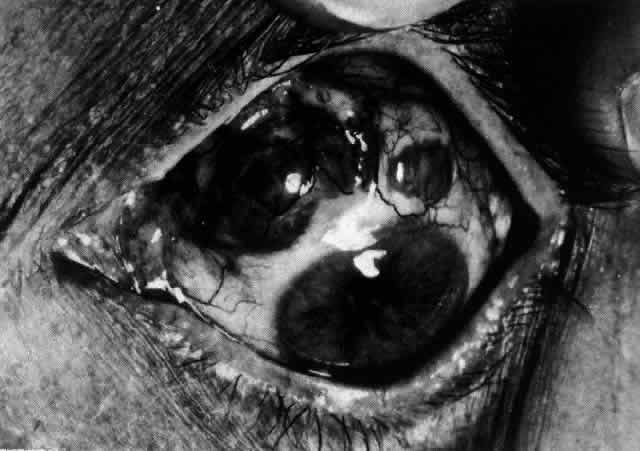

Posterior Scleritis

Because the posterior sclera is invisible, the diagnosis of posterior scleritis is made only if the anterior sclera is also involved or some other sign or symptom leads one to suspect it. Posterior scleritis is much more common than previously suspected, as recent clinical and pathologic studies have shown.19,28,29 There are two distinct forms of posterior scleritis. The first is usually associated with an anterior scleritis. This granulomatous disorder, like its anterior counterpart, can be diffuse, nodular, or necrotizing in character and is associated with the connective tissue diseases. The second form occurs in young patients of all races who are 9 to 40 years of age. It is always diffuse in character but is not associated with any systemic disorder. Both forms may cause uveitis if the inflammation affects the ciliary body, and in both forms the patient may develop exudative retinal detachments, choroidal folds, and swelling of the disc (Figs. 51 and 52). The granulomatous type may also involve the structures outside the globe, causing proptosis (Fig. 53), limitation of ocular muscle movement, and, uniquely, retraction of the lower lid on attempted elevation of the eye (Fig. 54). Diagnosis is with B-scan ultrasonography.

Fig. 51. Swelling of the optic nerve head and hemorrhage near the disc in a patient with posterior scleritis. The poor quality of the photograph is partly due to vitreous haze that accompanied the inflammation.

Fig. 52. Fundus appearance after resolution of exudative detachment in patient with severe posterior scleritis. Macula was affected and vision much impaired. (Watson PG: Management of scleritis. In: Recent Advances in Ophthalmology, Vol 5. London, Churchill-Livingstone, 1975)